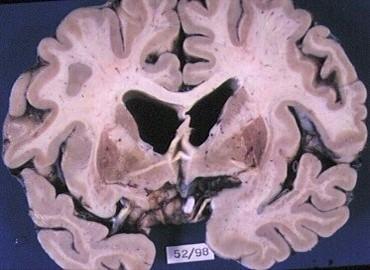

what is going on here

hydrocephalus

would dilated ventricles at autopsy signal hydrocephalus

YEP